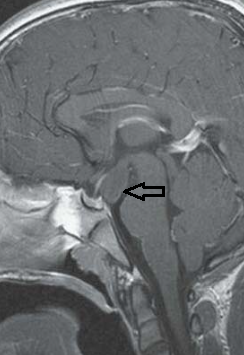

Tuber cinereum hamartoma

IRM

- Masse du tuber cinereum (entre corps mamillaires et tige pituitaire)

- IsoT1, Iso T2

- Pas de prise de contraste Gd+